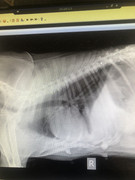

Сегодня собака была на обследовании - диагноз: эндометрит и опухоль.

Операция может дать шанс на жизнь Белке! Но делать ее нужно срочно!